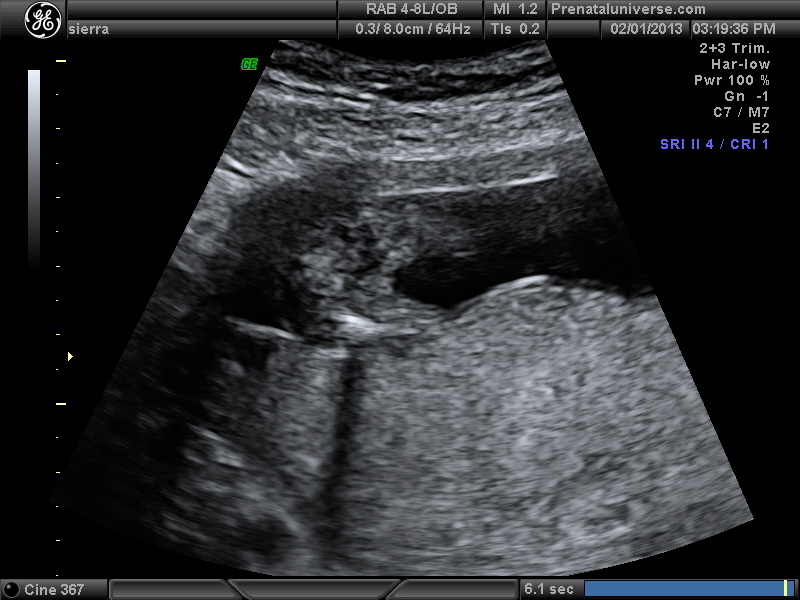

UPDATE!!!! Tech says girl. I was 16 w 1 day. Everyone agree? Nub shots were no help. Hoping this potty shot is more clear. In the video there were times it looked like there was something between legs but every still shot looks Girly I think:) Ty everyone :)

I'm curious about the area behind the black spot. I believe he said black spot is babys bladder. the area the arrow is pointing to looks girly but the area behind the black spot looks different??? thanks all